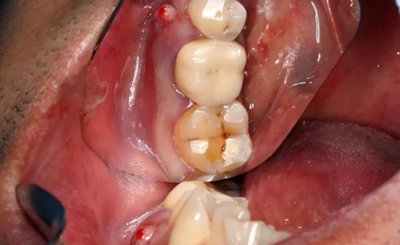

2、術(shù)前口腔內(nèi)照片

46牙烤瓷冠修復(fù),牙周紅腫,叩痛,松2度。骨吸收波及鄰牙,鄰牙牙周情況不佳,45牙松2度,47牙松1度。

(攝于2016年8月31日,反光板協(xié)助拍攝)